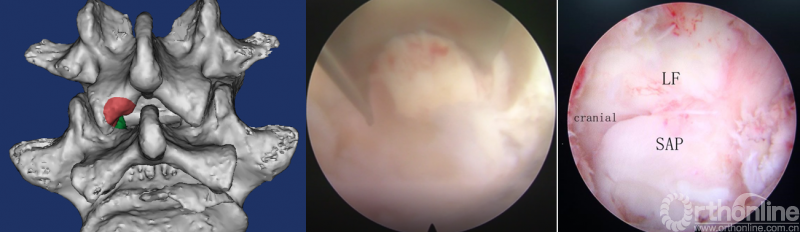

第三步“凿”:凿除部分下关节突,显露上关节突及黄韧带;

第四步“分”:分离上关节突及黄韧带;

第五步“咬”:咬除部分上关节突,显露椎间盘及神经根;

第六步“切”:切除椎间盘;